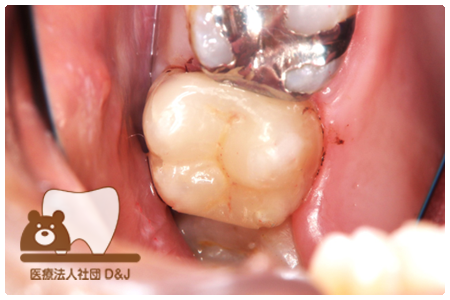

症例8フルジルコニアクラウン

治療前

治療中

治療後

29歳 女性

- 治療内容

- 銀歯からフルジルコニアクラウンへの修復

- 治療期間

- 根の治療含め3か月

- 費用

- 自費

フルジルコニアクラウン:77,000円(税込)

- その他の治療の費用は含まれておりません。

- リスク・副作用

- 強い衝撃が加わると欠けたり割れたりする可能性があります。また、噛み合わせの状態によっては脱離や周囲の歯への影響が出ることもあります。